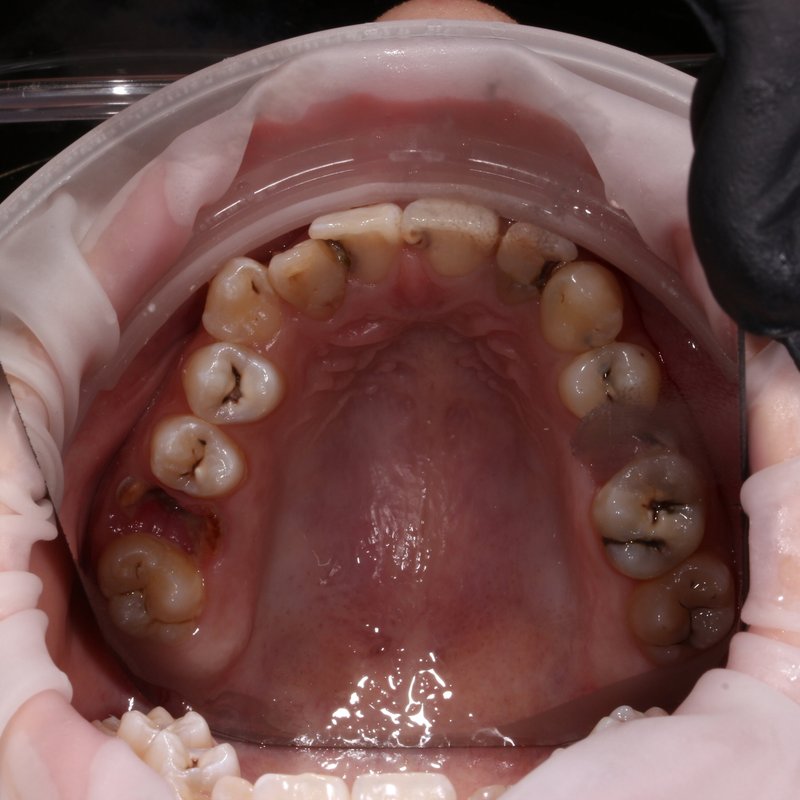

Фотогалерея